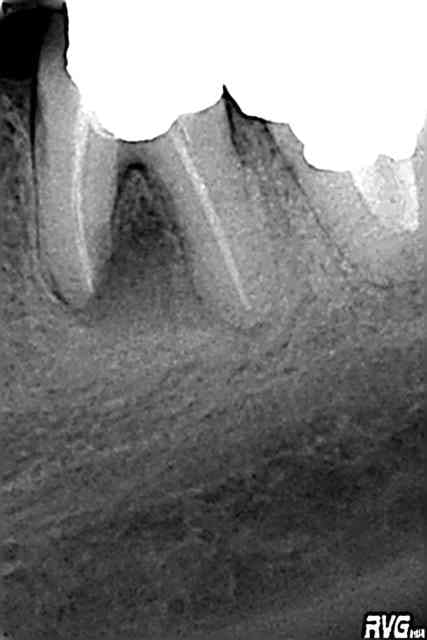

27/06/2009 à 18h28

ne vs disputez pas pr l'IC défunt or ou pas or,le tenon préfabriquée ou injecté

maintenant c'est RCR directe ou indirecte collée,mais ds tous les cas tenon flottant et collé

ds la seance aujourdhui, avec provisoire mise en place

mais la dent va t'elle recupérer?...

2 heures chrono: ameli suis je assez productive pr être embauchée avec un bon indice?:)